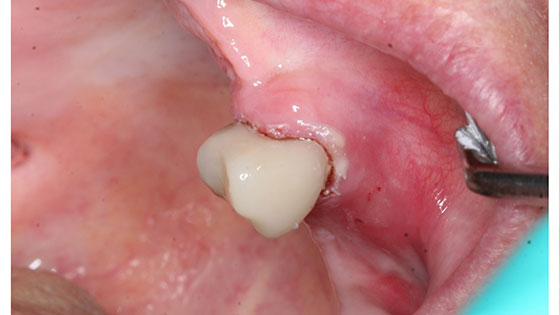

Composite Fillings Along Gum Line on Upper Teeth

Composite Fillings Along Gum Line on Upper Teeth